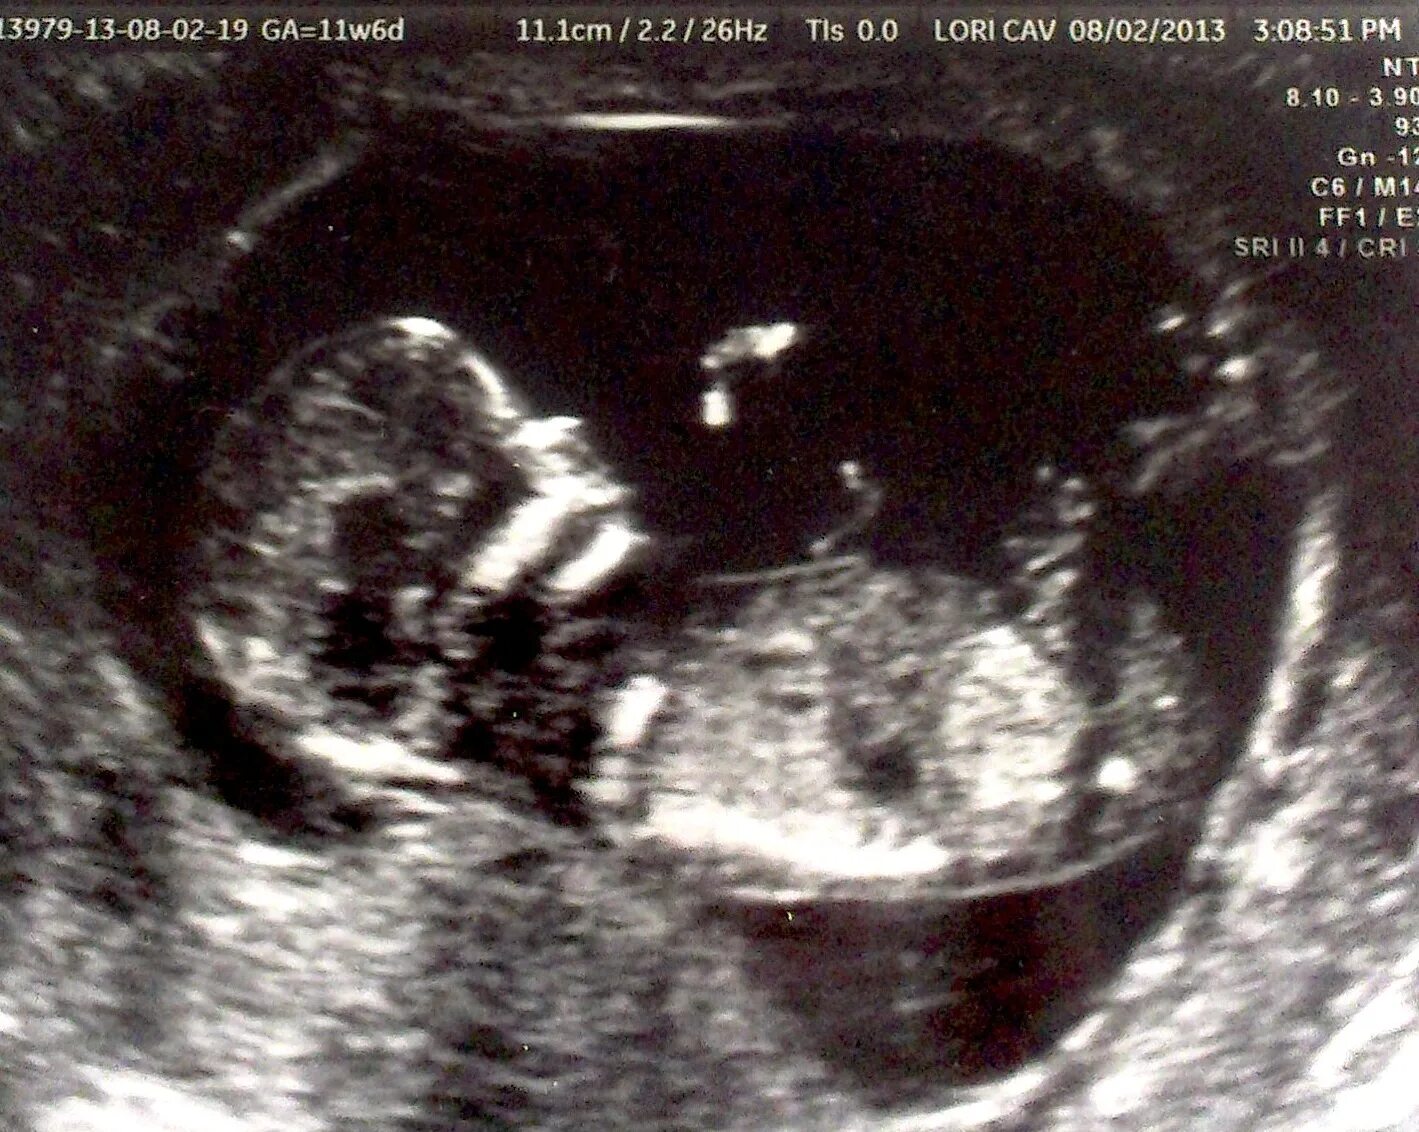

Ребенок в 13 недель